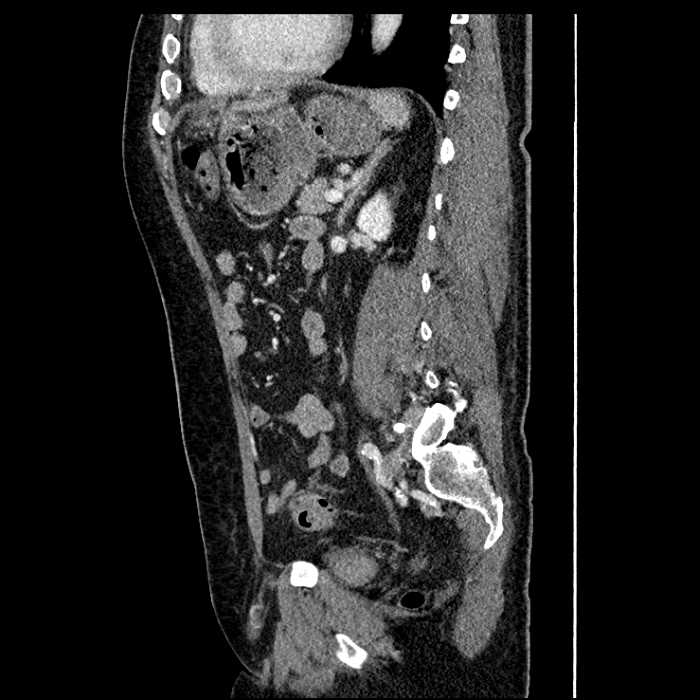

• Large fluid density structure in hepatic segments 7 and 8 measuring 10 x 7 x 7 cm with internal septation and circumferential ill-defined low density compatible with edema

• Peripherally enhancing subcapsular collections along the anterior margin of the left hepatic lobe measuring 3 x 1 cm and 2 x 1 cm

• Mild mural thickening of a segment of the sigmoid colon with adjacent fat stranding and a 1.5 cm fluid and gas collection along the tip of an inflamed diverticulum

• Loss of the normal fat plane between this collection and adjacent loops of small bowel, which demonstrate mural thickening

Acute sigmoid diverticulitis complicated by a small contained perforation and a large abscess in the right hepatic lobe. Additional small subcapsular abscesses along the anterior margin of the left hepatic lobe.

Additionally, loss of the normal fat plane between the peridiverticular collection and adjacent thickened loops of small bowel raises the potential for an enterocolonic fistula.

• The classic CT imaging appearance is a double target sign with internal low density surrounded by an internal enhancing rim (capsule) and a low density external rim (edema)

Hepatic abscess showing the double target sign with low density internally surrounded by a thin inner enhancing rim (red arrow) and ill-defined outer low density rim (yellow arrow). Blue arrow indicates an internal septation. Red arrows: additional smaller subcapsular abscesses. Red arrow: focal contained perforation associated with diverticulitis.